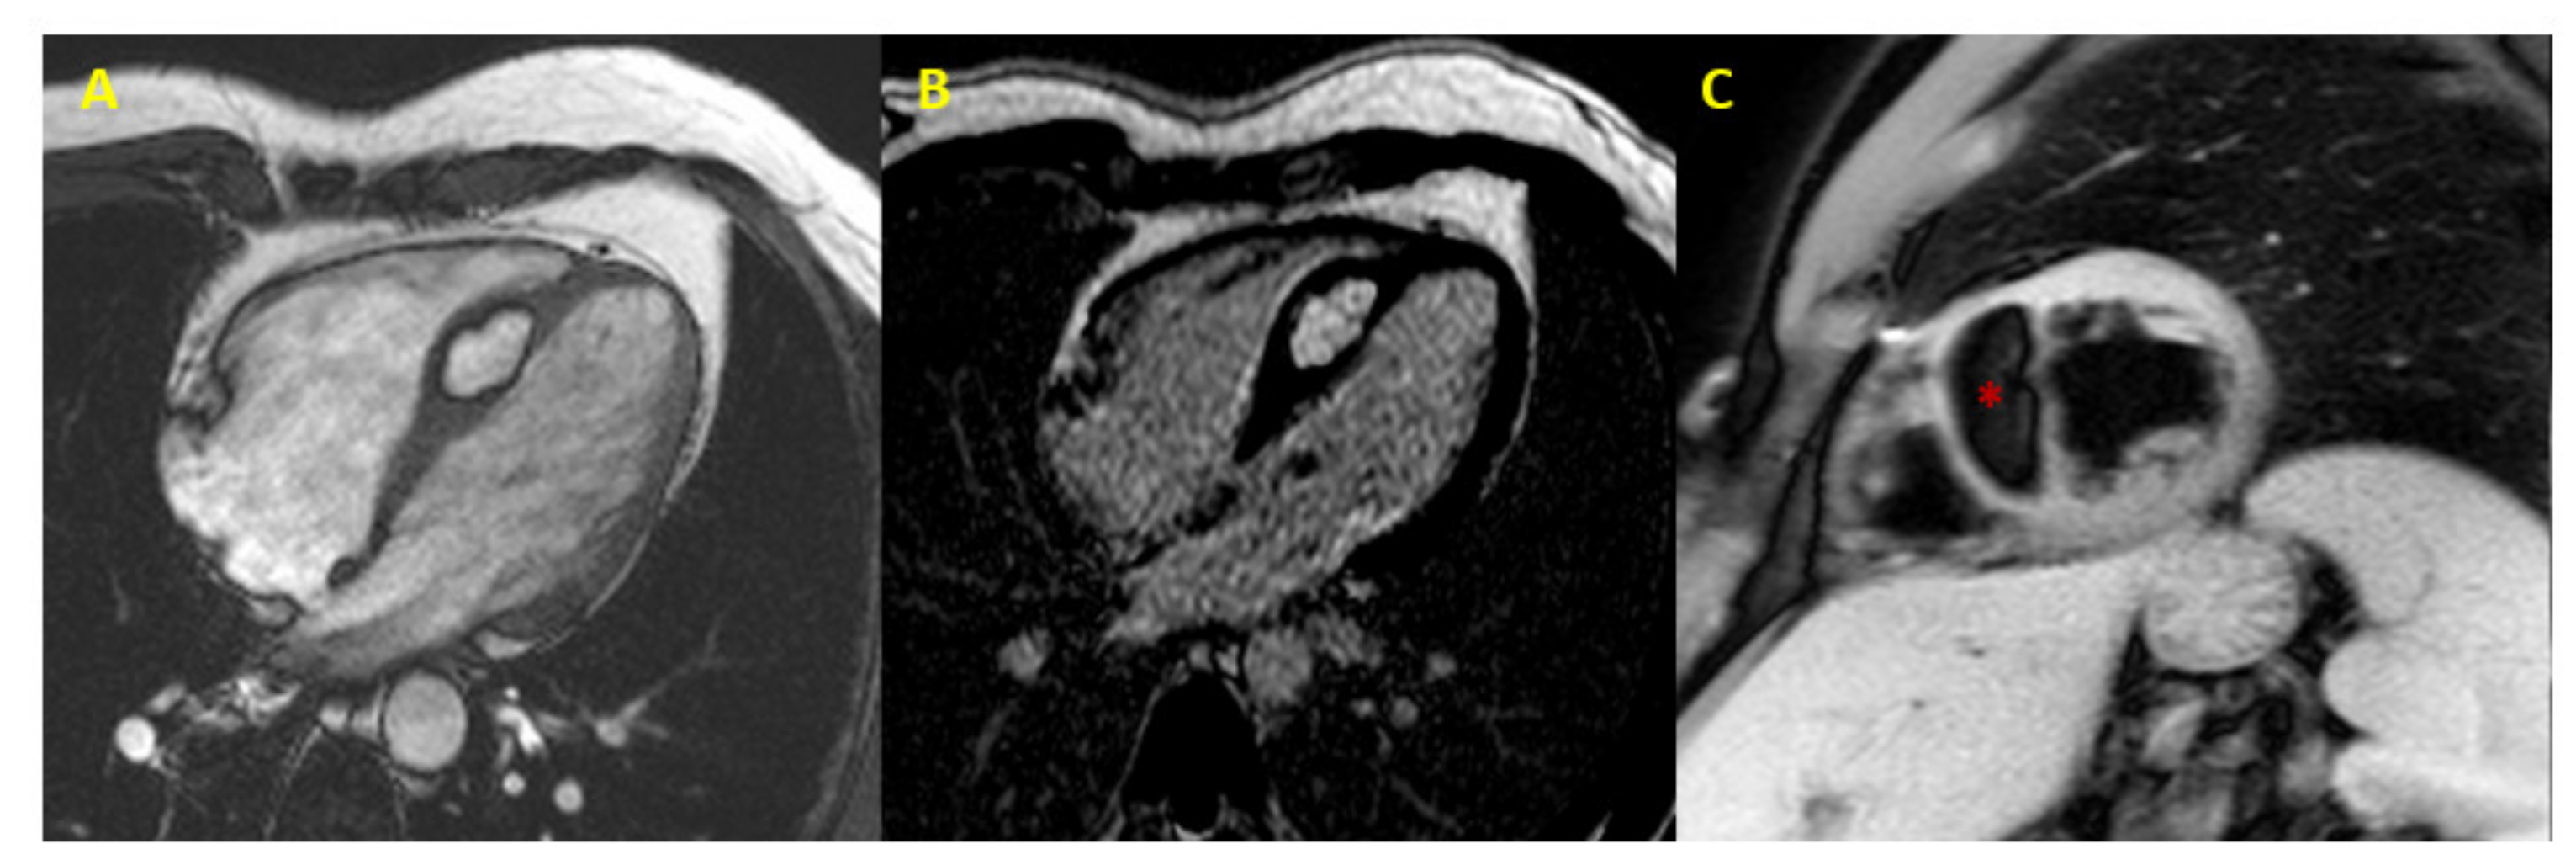

| Myxoma | Left atrium, right atrium, interatrial septum | Splinde-shaped cells (myxoma cells), calcification can be present | T1 iso/hypointense, T2 hyperintense, heterogeneous late contrast enhancement of >50% of the mass area | 5% are a manifestation of the Carney complex. In case of haemorrhage and haemosiderin deposition, hypointense in all sequences | [24] |

| Lymphoma | Right atrium | Malignant lymphocytes | T1 and T2 isointense, heterogeneous enhancement | Highly abnormal T2 relaxation times (up to 140 ms) with T2 -mapping | [29,30,31,32,33,34,35] |